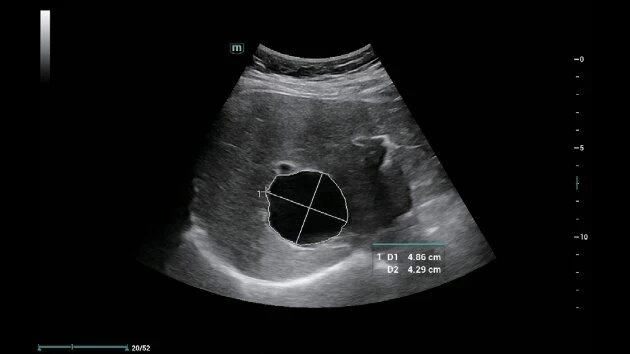

Ультразвуковая система Mindray Consona N6 построена на революционной платформе ZST+, которая представляет новый подход к ультразвуковой визуализации, обеспечивая исключительное качество изображений.

• Уникальный метод анализа данных на основе информации от каждого канала

• Оптимальный баланс между пространственным и временным разрешением

• Улучшенная однородность визуализации тканей

• Непрерывное совершенствование качества изображения